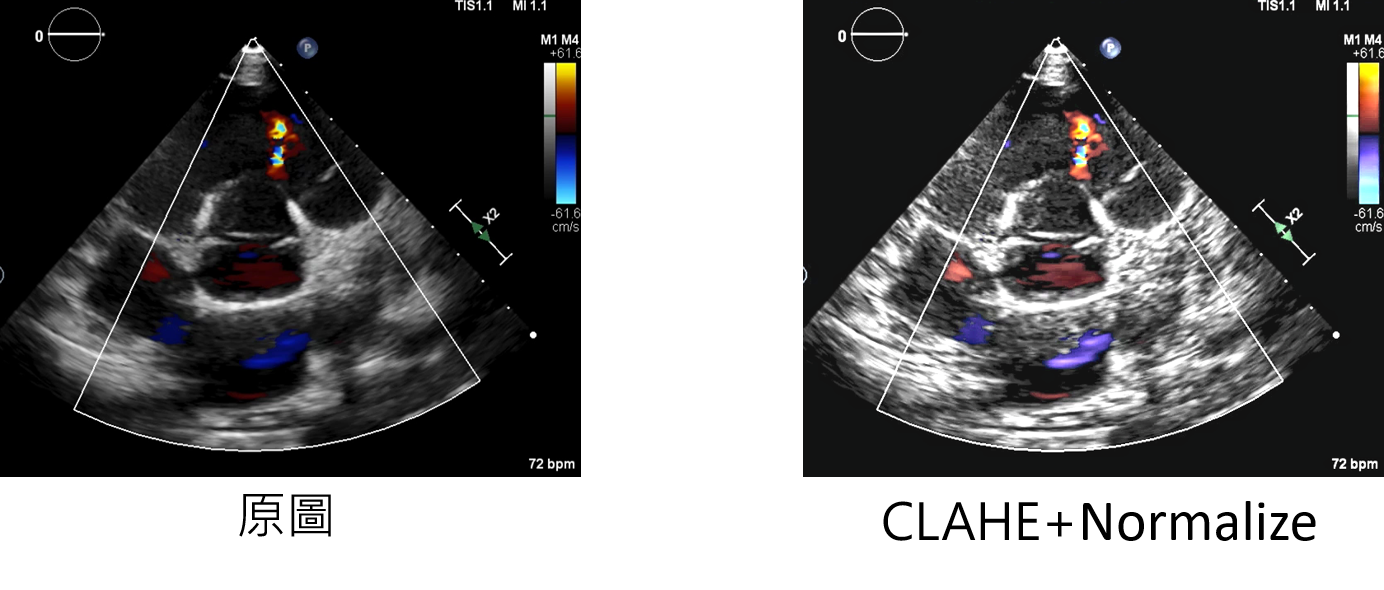

CLAHENormalize:增強方法

clahenum:設定每次處理的大小

輸入範例:

datagen=CustomDataGenerator(fun="CLAHENormalize",clahenum=40,dtype=int)

*下圖為CLAHE-clahenum=40+normalize與原圖的對比